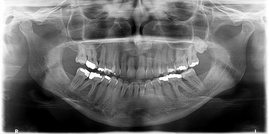

RECORDS